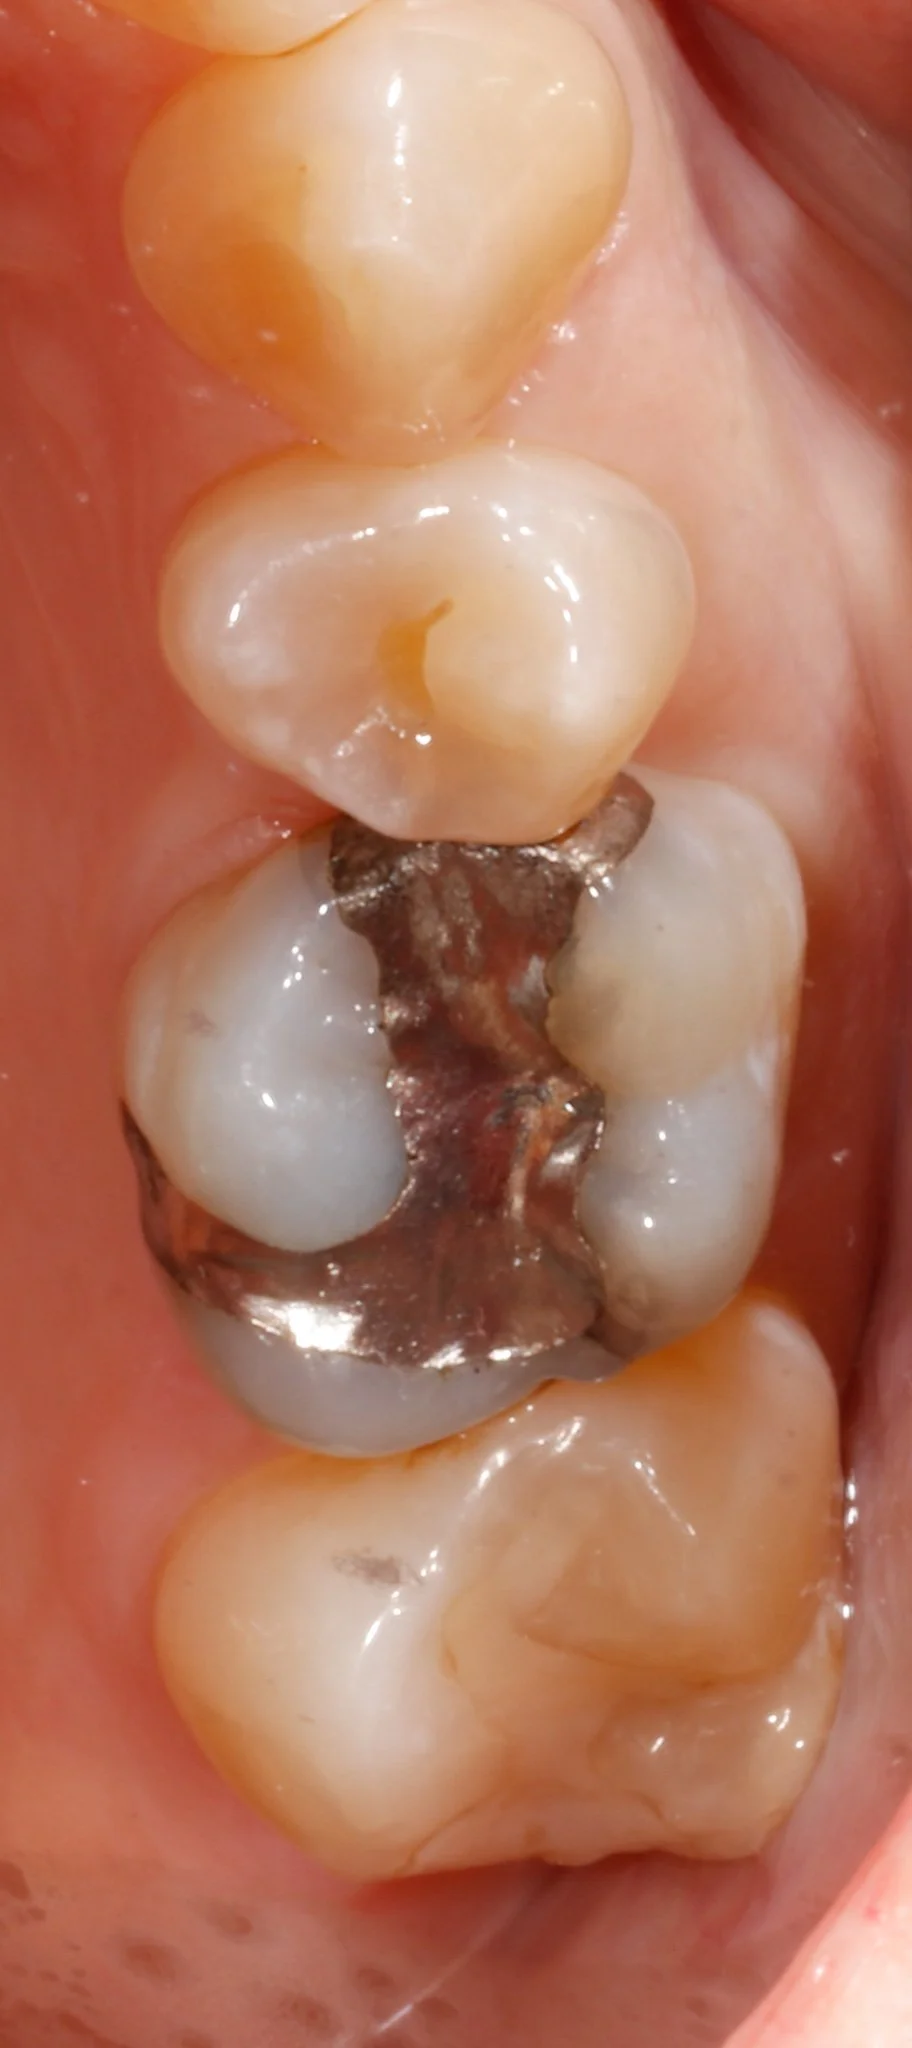

Close-up of a person's molar teeth with leakage, cracks and decay.  Prior to restorative treatment.

Before: Large silver fillings with leakage and cracks

Close-up of a person's molar teeth restored with gold and composite resin.

After: Gold partial coverage restoration to protect from further fracture